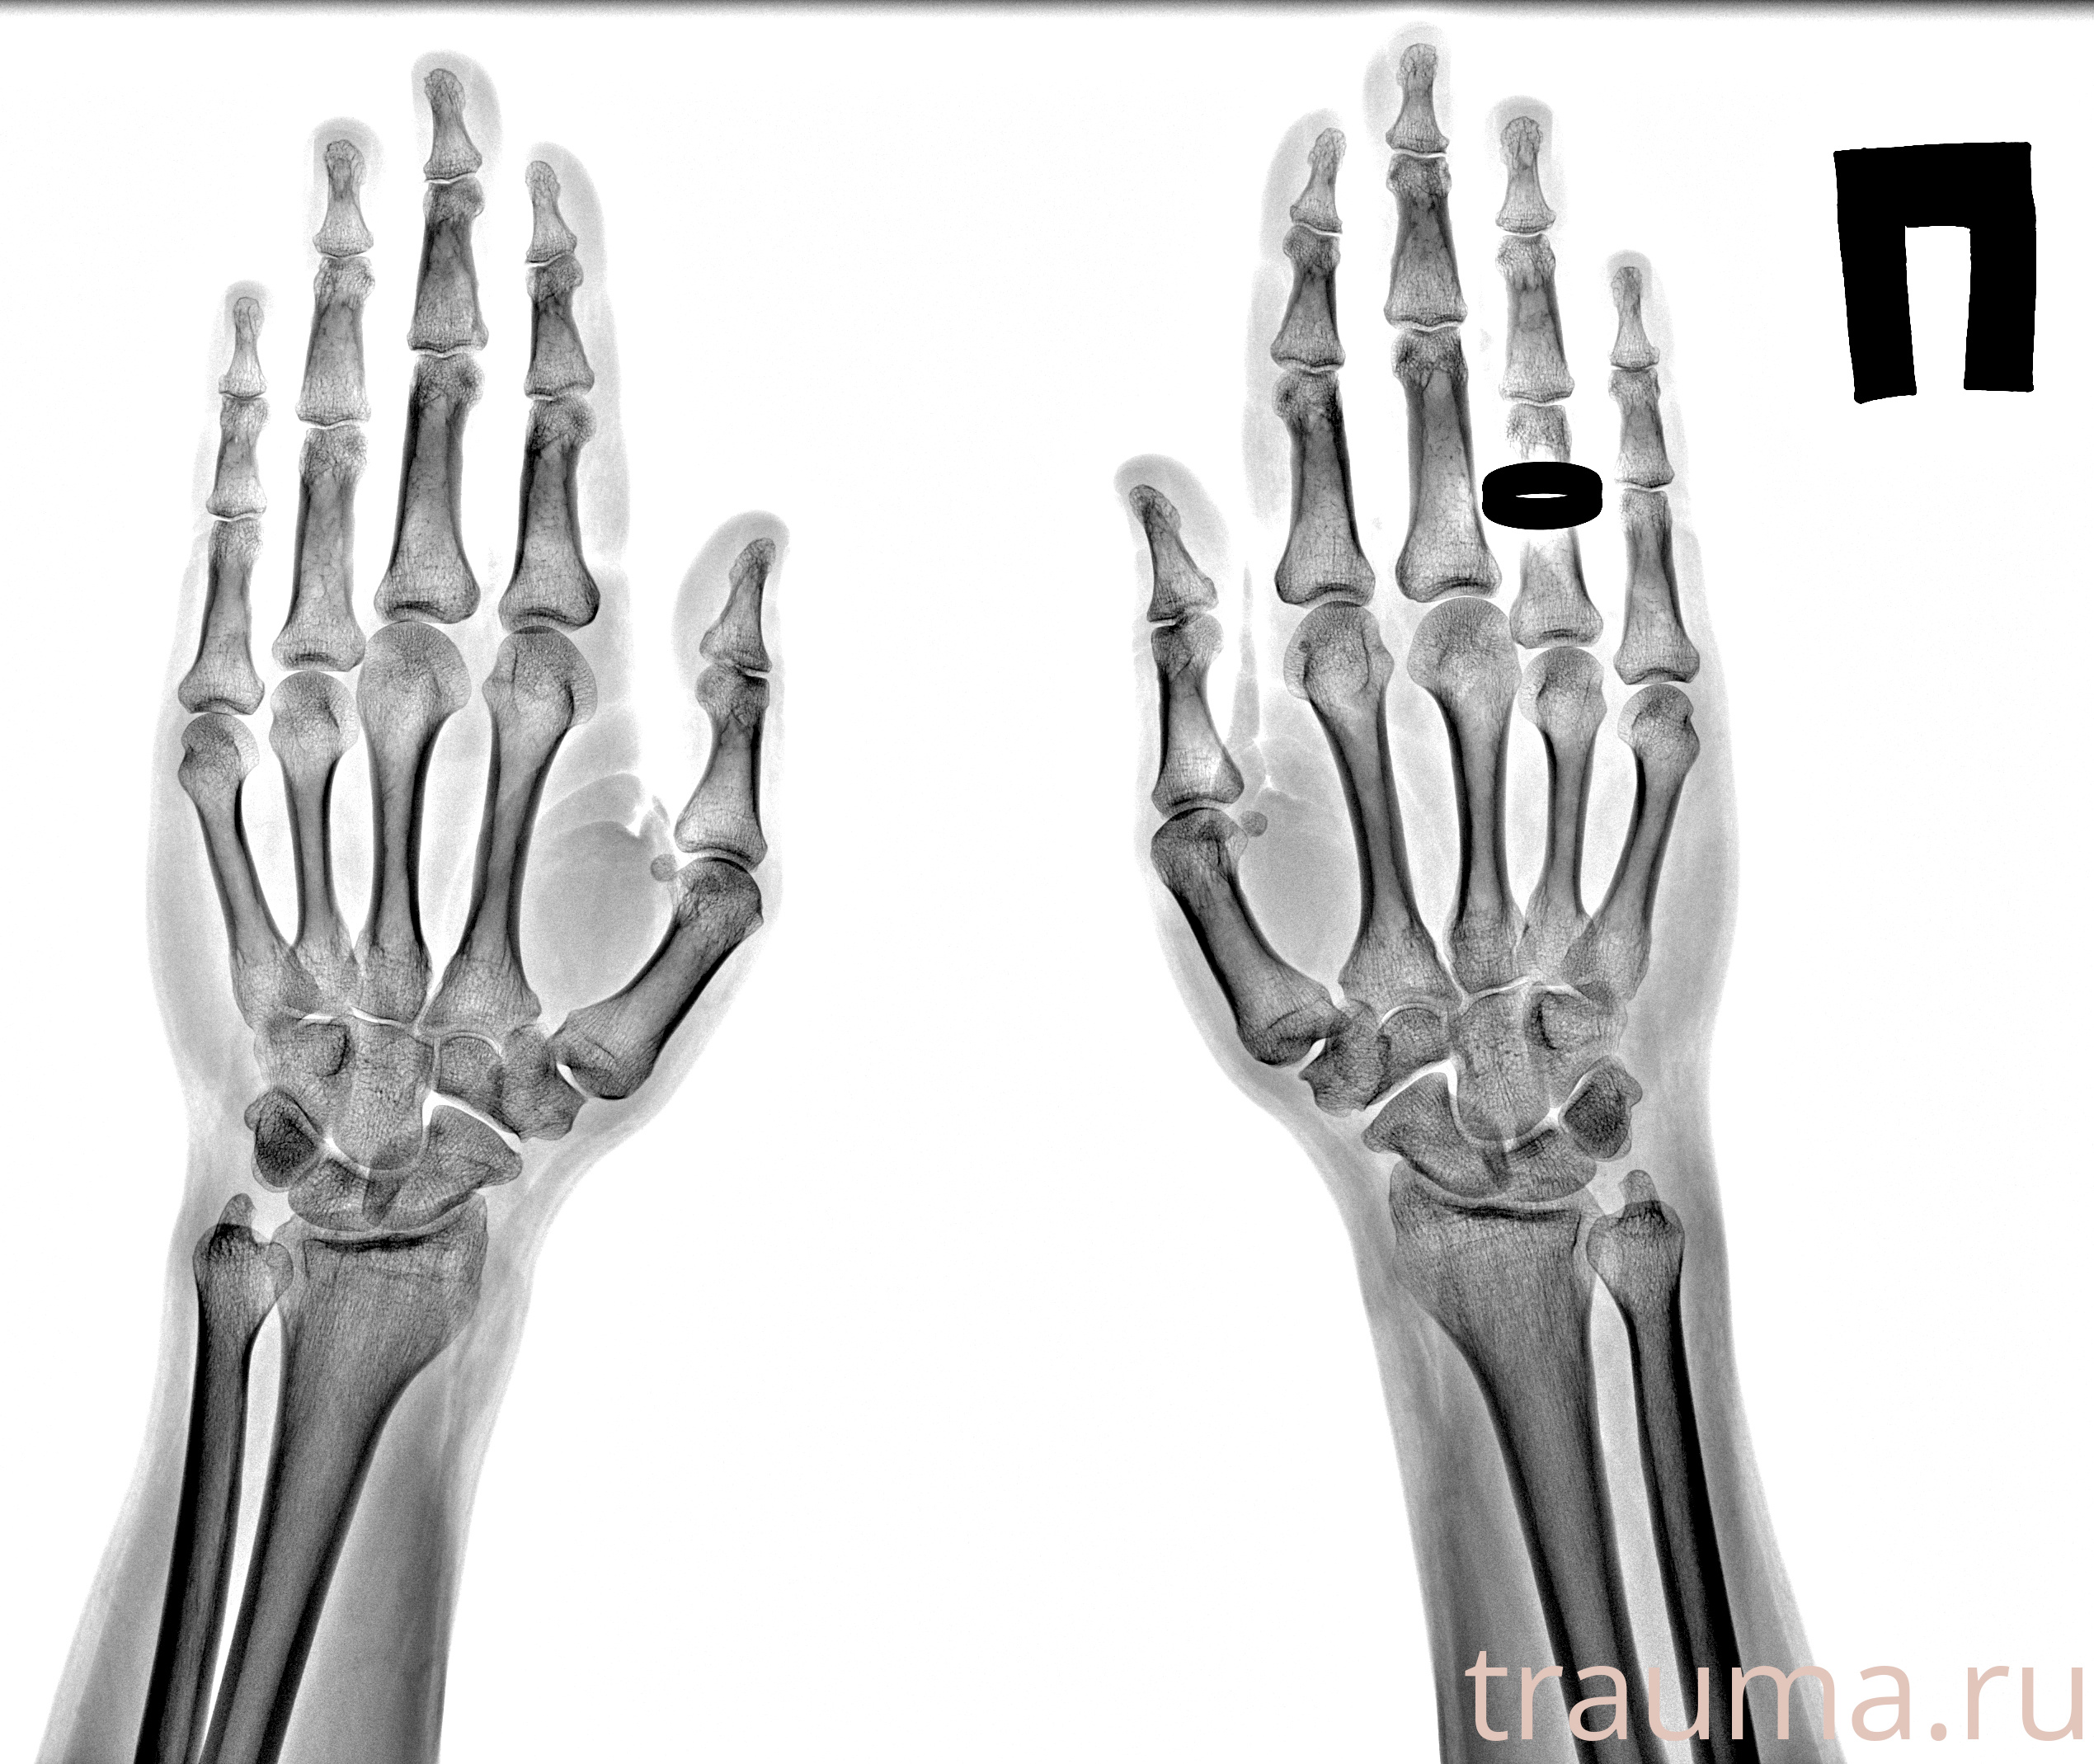

Рентген на дому: по вашему адресу приезжает врач-рентгенолог, травматолог-ортопед с мобильным рентгеновским аппаратом, проводит диагностику травмы или заболевания, делает необходимые рентгенограммы, дает рекомендации по дальнейшему лечению. Получить качественные снимки в домашних условиях возможно благодаря уникальной методике, разработанной МосРентген Центром для института  Склифосовского